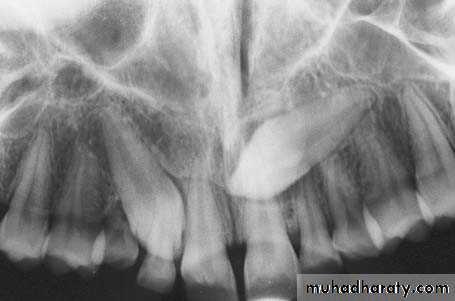

Radiograph showing impacted maxillary canines with a palatal localization

Definition: Is the most common supernumary (extra) tooth. It is located in the maxilla in the midline (hence the special name which means "middle tooth").

Mesiodens tooth

Radiographic features

classified into eumorphic (similar to a normal-sized central incisor) and dysmorphic

three common dysmorphic shapes

• conical or peg shaped (most common ~70%)

• tuberculate (more than one cusp or tubercle)

• supplemental (duplication of a normal tooth)

55% grow in the downward position (35% are inverted and 7% are horizontal)

most remain impacted but 25% will erupt (usually eumorphic or conical shape)